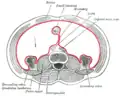

Horizontal disposition of the peritoneum in the lower part of the abdomen

Horizontal disposition of the peritoneum in the lower part of the abdomen -